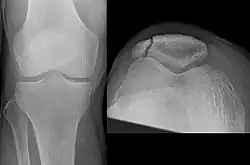

| A fracture of the patella seen on a lateral view | |

| Diagnostic method | Based on symptom, confirmed with X-rays.[3] |

It typically results from a hard blow to the front of the knee or falling on the knee.[1]The patella can also be fractured indirectly. For example, a sudden contraction of the quadriceps muscle in the knee can pull apart the patella.[1]Diagnosis is based on symptoms and confirmed with X-rays.[3] In children an MRI may be required.[3]

Diagnosis is based on symptoms and confirmed with X-rays.[3] In children an MRI may be required.[3]